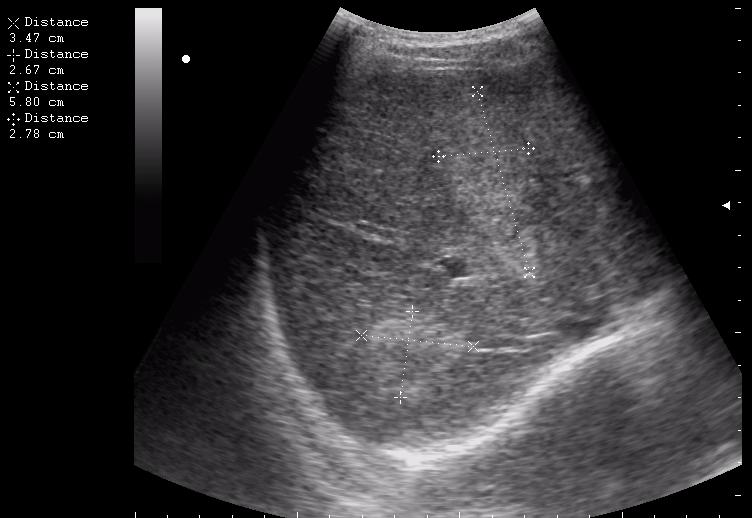

сегодня был селезёночный день.